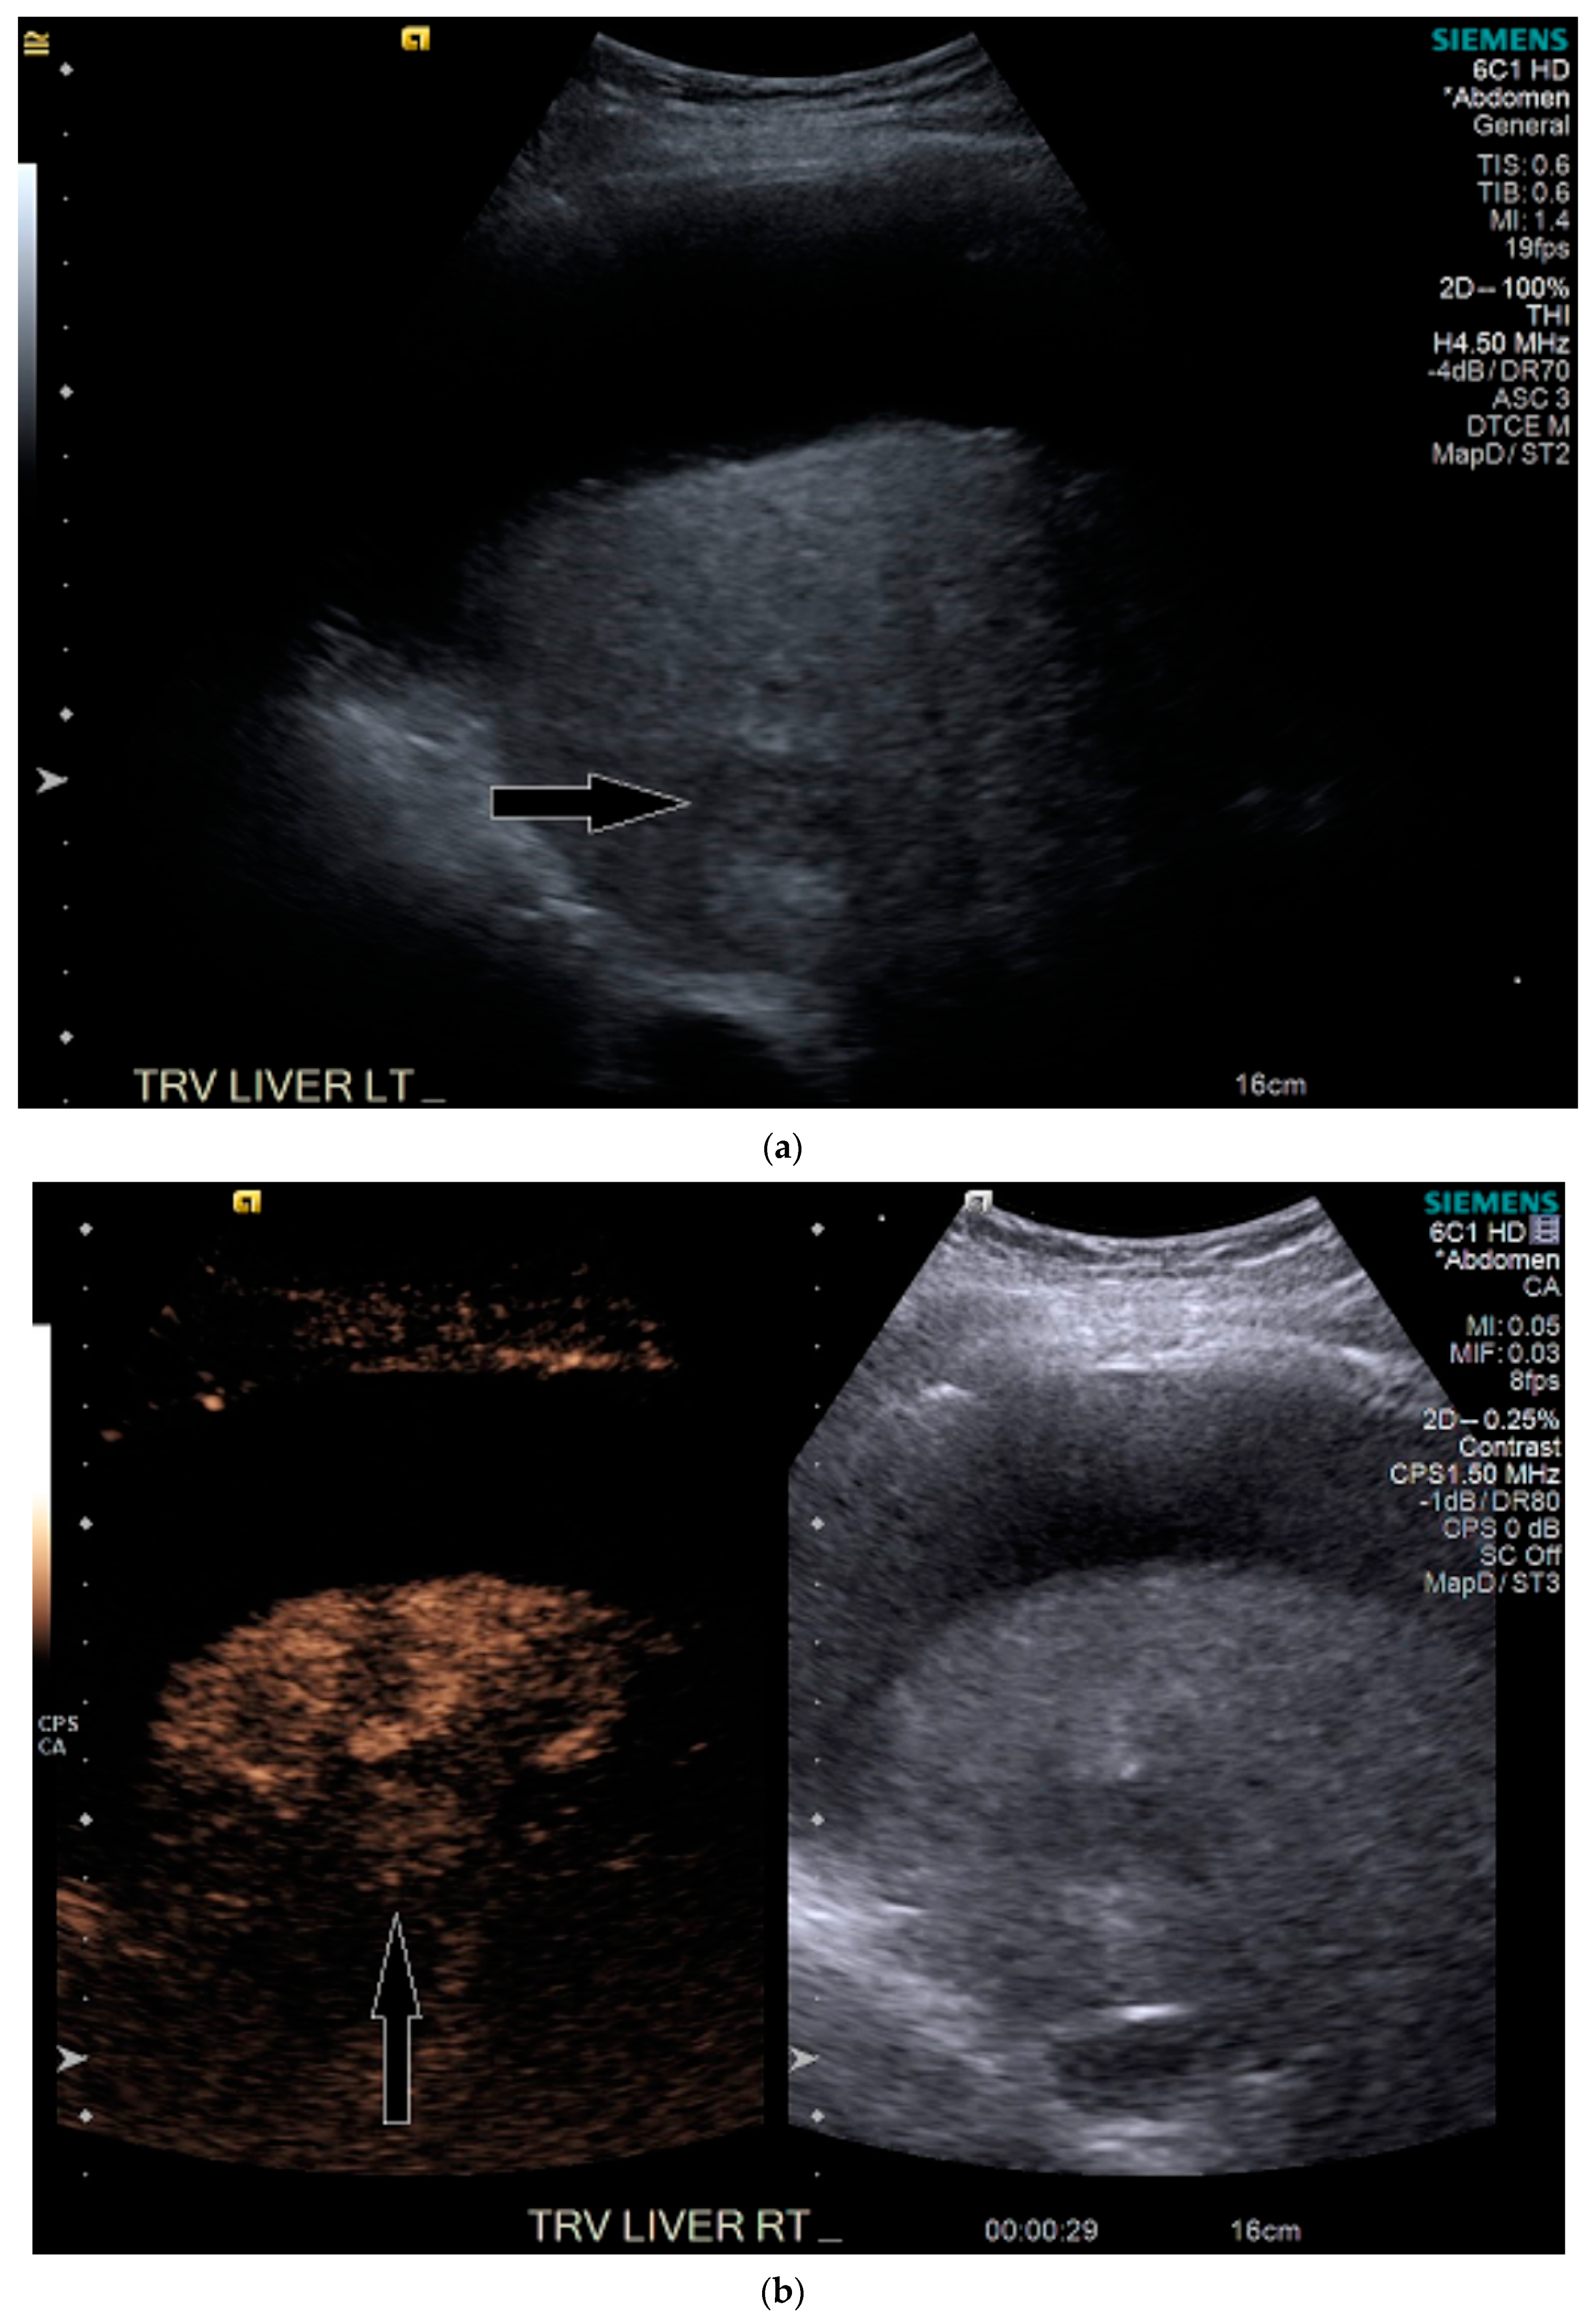

3.2. Case 2